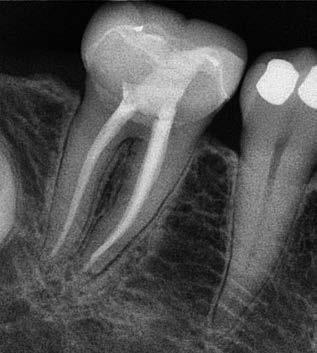

Gyökéramputációt főként a furkáció érintett nagyőrlő fogak ellátása során szoktunk alkalmazni. Derks és mtsai. vizsgálatában a gyökéramputált nagyőrlő fogak közel 80%-a 20 évvel a beavatkozás elvégzését követően is megtartott volt. 1998 októberében egy 39 éves férfi páciens a jobb alsó kvadránsban jelentkező ínyérzékenység miatt kereste fel rendelőnket. A klinikai vizsgálat során jobb alsó első és második nagyőrlő fog között (46–47) nagy kiterjedésű csontveszteséget észleltünk. Ettől eltekintve a teljes fogazat parodontális státusza megfelelőnek bizonyult. A jobb alsó kvadránsban végzett szenzibilitás vizsgálat során arra az eredménye jutottunk, hogy a 46-os fog vélelmezhetően elhalt (10. ábra).

A páciens beleegyezését követően a 46-os fog disztális gyökere, a disztális gyökér felett lévő koronális rész megőrzése mellett rezekcióra került (11. ábra). A rezekciót követően a referáló orvos a 46. és 47. fogak koronáját Ribbond szalag és kompozit segítségével egymáshoz rögzítette. A sebészi beavatkozást követően 22 évvel készült kontrollfelvételen a lézió csontos telődése, kortikális csontállomány kialakulása, valamint a furkáció körüli csontos regeneráció volt megfigyelhető (12. ábra) A károsodott fogak megtartására szolgáló lehetőségek fejlődésének, valamint az implantátumok behelyezésével kapcsolatos rizikófaktorok jobb megértésének köszönhetően ma már más szemmel vizsgáljuk a fogak eltávolításának szükségességét. A kérdéses prognózissal vagy a kis protetikai értékkel rendelkező fogak eltávolítása előtt mindig érdemes felmérni az ezzel elérhető lehetséges előnyök nagyságát. A kemény- és lágyszöveti pótlás lehetőségeinek fejlődésével, a PRF elérhetőségével, a minimálinvazív sebészeti módszerek és az operációs mikroszkópok elterjedésével, valamint a varróanyagok és varrat technikák egyre kifinomultabbá válásával ma már alaposan el kell gondolkodnunk az előtt, hogy egy fogat egy implantátum behelyezése érdekében eltávolítsunk. Mára sokkal kedvezőbb prognózist és sokkal nagyobb sikerességet tudunk elérni a korábban menthetetlennek gondolt fogak kezelése során.